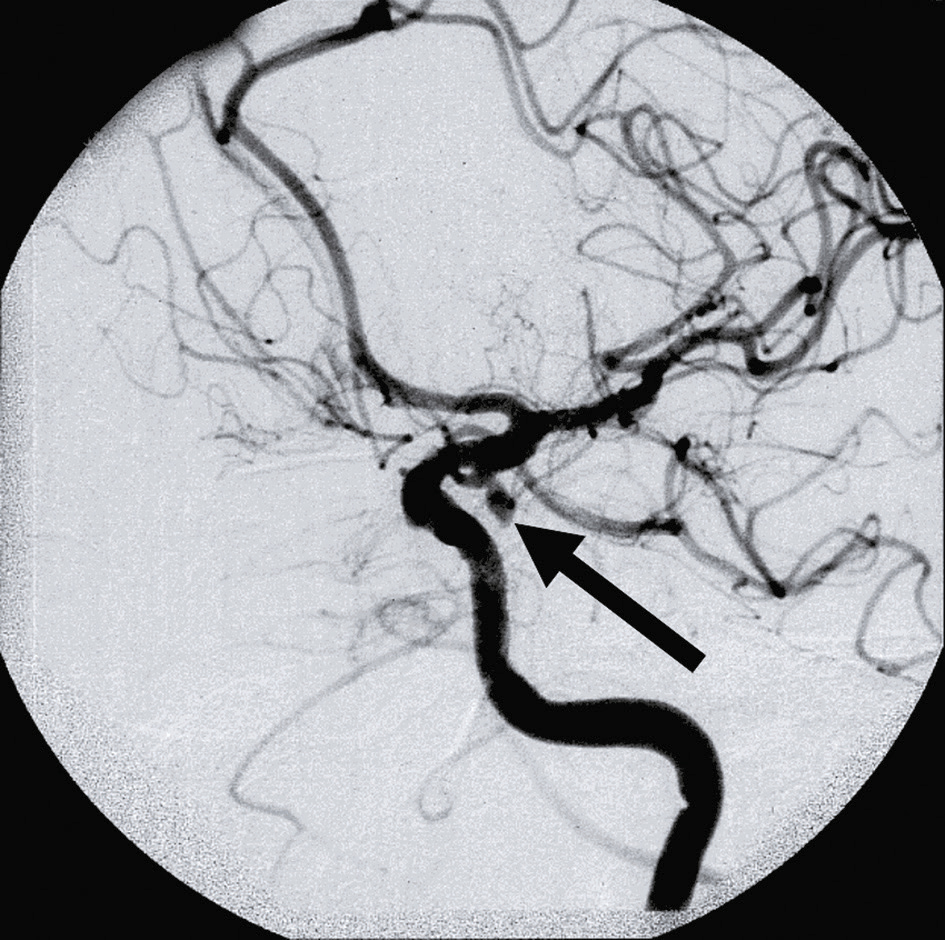

Une artériographie est réalisée (fig. 13.9) et le traitement endovasculaire doit être réalisé au plus tôt, dans les heures qui suivent le diagnostic.

Fig. 13.9

Anévrisme supraclinoïdien responsable d’une paralysie aiguë douloureuse intrinsèque et extrinsèque du III gauche (vidéo 13.2

).L'angiographie cérébrale de cette image montre un anévrisme supraclinoïdien, situé au niveau de la partie supraclinoïdienne de l'artère carotide interne. Un anévrisme est une dilatation anormale d'un vaisseau sanguin. Cet anévrisme spécifique provoque une paralysie aiguë douloureuse intrinsèque et extrinsèque du nerf crânien III gauche, également connu sous le nom de nerf oculomoteur. La paralysie du nerf III affecte les muscles qui contrôlent les mouvements de l'œil et les muscles de la paupière. Les symptômes comprennent la diplopie (vision double), la ptose (chute de la paupière) et une douleur intense. L'angiographie, une technique d'imagerie médicale, est cruciale pour visualiser l'anévrisme et planifier son traitement. En résumé, un anévrisme supraclinoïdien entraîne une paralysie aiguë douloureuse du nerf III gauche, affectant les mouvements de l'œil et de la paupière, avec des symptômes tels que la diplopie, la ptose et une douleur intense. La visualisation précise de l'anévrisme par angiographie est essentielle pour le diagnostic et la planification du traitement.

Vidéo 13.2. A Paralysie complète intrinsèque et extrinsèque du III gauche.

La patiente présente un ptosis, un strabisme externe, une paralysie d’adduction, d’élévation et d’abaissement ainsi qu’une mydriase non réactive à la lumière. Cette patiente présentait un anévrisme supraclinoïden gauche (fig. 13.9).